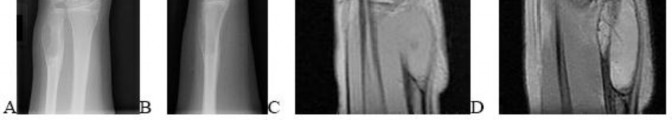

A 15-year-old male presents with deep knee pain awakening him at night. Radiographs show a permeative destructive lesion in the distal femoral metaphysis with a 'sunburst' periosteal reaction and Codman's triangle.

Biopsy confirms high-grade conventional osteosarcoma. What is the most critical prognostic factor for long-term overall survival in this patient?

Explanation

For localized high-grade osteosarcoma, the most important prognostic indicator is the histologic response to neoadjuvant chemotherapy. This is evaluated during the definitive resection. A 'good response' is typically defined as greater than 90% or 99% tumor necrosis. Patients who achieve this level of necrosis have a significantly improved disease-free and overall survival rate compared to 'poor responders' who have extensive viable tumor cells remaining.